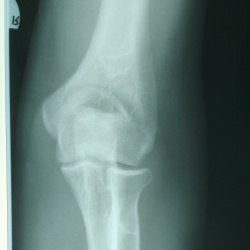

Мужчина, 48. Жалобы на боли в правом локтевом суставе. Травм не было. Работа связана с физическим трудом.

На боковом снимке смущается обведенный округлый участок. На...